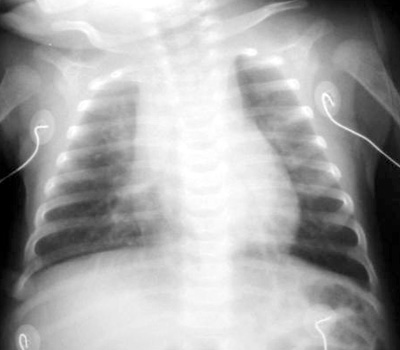

Bordetella pertussis pneumonia is encountered less frequently because of vaccination, but it is still relatively common. In the fall of 2001, there was a small epidemic of 56 cases in Albemarle County, Virginia. The diagnosis is usually made on the basis of the characteristic "whooping cough" and confirmed with a PCR test. The classic finding on CXR is a "shaggy heart".

Example of a "shaggy heart" on CXR in a patient with Bordetella pertussis pneumonia.